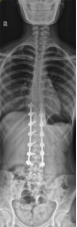

8. 机器人导航辅助下脊柱侧弯矫正技术

脊柱侧弯是一种复杂的脊柱三维畸形,其中以青少年特发性脊柱侧凸最常见。性爱视频

在浦口地区率先开展机器人导航辅助下脊柱侧弯矫正术,实现了脊柱侧弯手术准确、微创、智能化的突破,获得了良好的效果。还有老年人退变性侧弯,机器人亦可精准置入困难椎弓根螺钉,误差只有0.3mm。